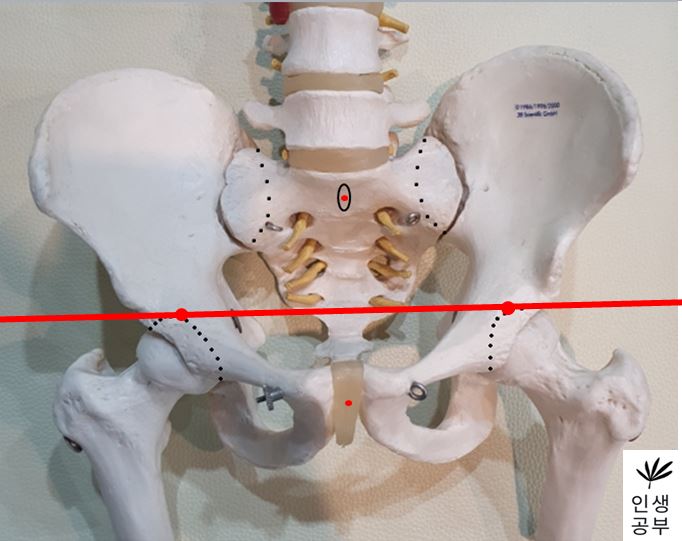

2) 대퇴골두(Femoral head) 최상단에 양쪽에 각각 한개씩 점을 찍어줍니다.

3) 두 점을 연결하는 선을 긋습니다. 이 선의 이름은 대퇴골두선(FHL : Femur Head Line)이라고 합니다.

4) 1번째나 2번째 엉치뼈 결절(sacral tubercle) 정가운데 점을 찍어줍니다.

5) 치골결합(pubic symphysis) 정가운데에도 점을 찍어줍니다.